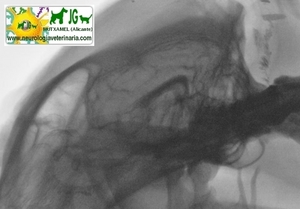

VENTRICULOGRAFÍA con inyección de contraste en la cisterna magna |